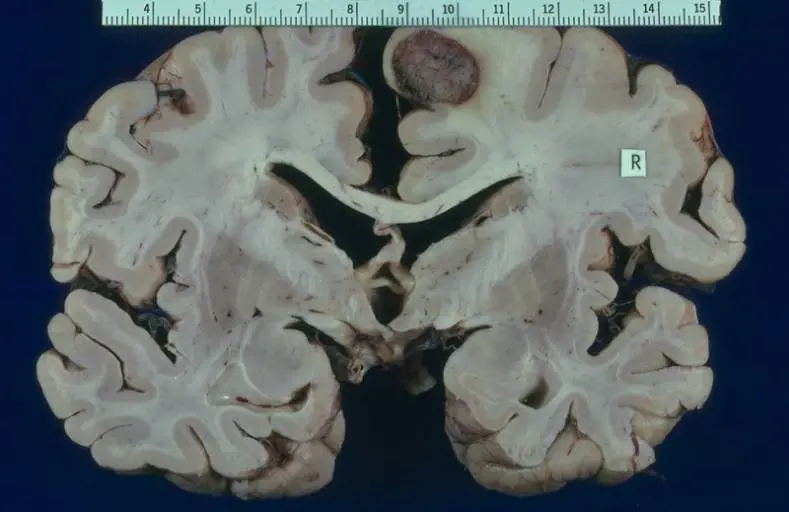

Tipica dell'età pediatrica, questa forma di cancro colpisce ogni anno due persone su un milione. Tale quota rappresenta l'1% di tutte le neoplasie del sistema nervoso centrale. La sopravvivenza a 5 anni dalla diagnosi è di poco superiore al 60%. Valori più alti (tra il 70% e l'80%) si registrano, invece, limitatamente ai soggetti adulti. Il medulloblastoma è un raro tumore al cervello che, molto probabilmente, prende origine dalle cellule progenitrici indifferenziate del cervelletto. Appartenente alla categoria dei carcinomi primitivi neuroectodermici dell'encefalo, è questa una neoplasia a crescita molto rapida e con un elevato potere infiltrativo.